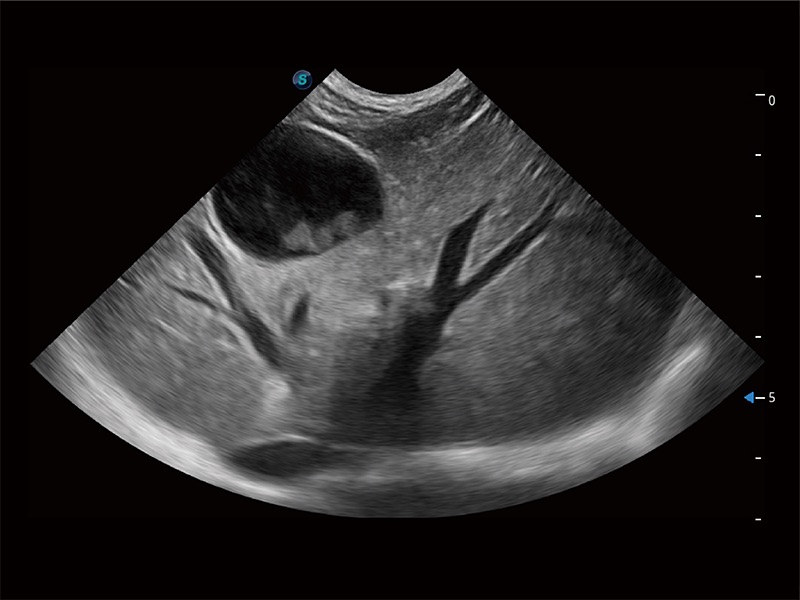

ProPet 80 专为动物医生设计,对不同的动物体型和生理结构作出了针对性的优化。通过动物影像专用软件,可满足个性化的应用需求,帮助动物医生获得更精确的诊断数据。

针对宠物、马科、农场动物、实验室动物和异宠等20多种动物种类,预置丰富的动物注释及动物体标库。

ProPet 80 全新的动物超声智能软件和丰富的探头群,为动物医生提供了高清晰度和精细分辨率的图像,无论在宠物、马科、畜牧还是实验室动物等应用中都可以轻松应对,为您的日常工作带来满意的体验。